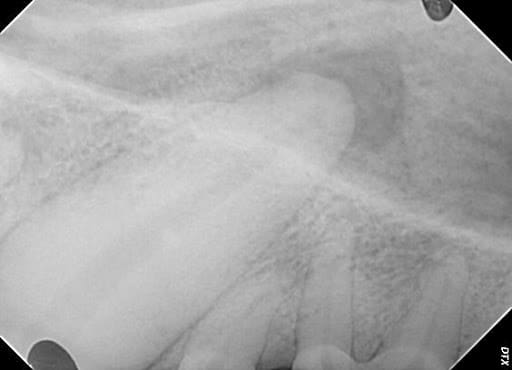

Figure 1 – An upper canine (fang) tooth radiograph with a large abscess around the apex of the tooth root.